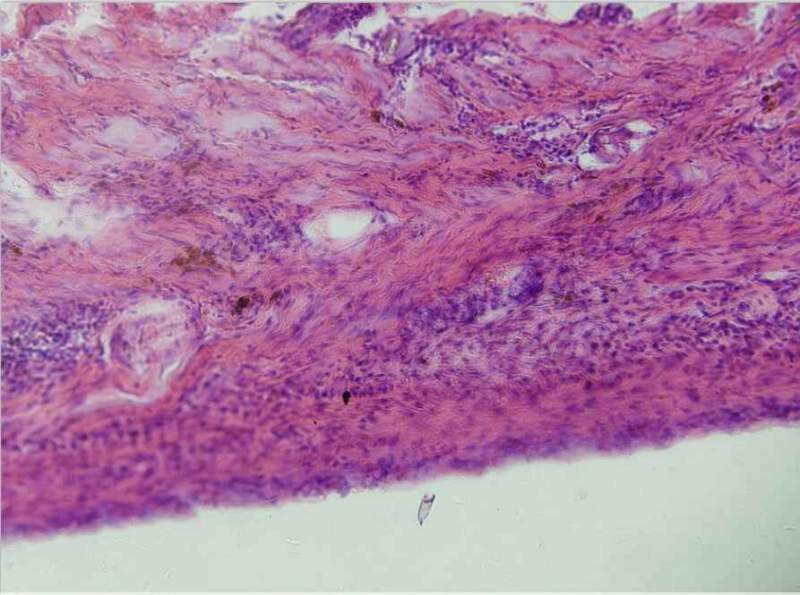

Çë°ïæ¿´ÏÂÕâÇÐÆ¬ÄÜ˵Ã÷ʲôÂ𣿺ÚÉ«µÄÊÇÎÒÇÐÆ¬¼¼ÊõÎÊÌâÂ𣿠ÒÑÓÐ2È˲ÎÓë

ÕâÈýÕÅÊDz»Ò»ÑùµÄ£¬Ò»¸öÊÇ´ÆÊóÓвÄÁÏ£¬ÁíÍâÁ½¸ö·Ö±ðÊÇ´ÆÐ۵Ŀհס£ ·¢×ÔСľ³æAndroid¿Í»§¶Ë |

Â¥Ö÷£¬ÄãµÄÇÐÆ¬ÖÊÁ¿È·Êµ²»Ì«ºÃ£¬Ê×ÏÈÇÐÆ¬Ê±Óе¶ºÛ£¬ÔÙ¾ÍÊÇÇÐÆ¬Ì«ºñ£¬ÇÐÆ¬²»ÔÚÍ¬Ò»Æ½Ãæ£¬×Ðϸ¿´µÚ¶þÕž۽¹²»ÔÚÍ¬Ò»Æ½Ãæ£¬È¾É«Ê±Ã»ÓÐÏ´¸É¾»£¬ÓÐÔÓÖÊ£¬ÄÇЩºÚÉ«µÄÓ¦¸ÃÊÇÔÓÖÊ£¬Ò²ÓеãÏñȾɫ²½Öè²»¹æ·¶Ôì³ÉµÄ ·¢×ÔСľ³æIOS¿Í»§¶Ë |

ÇÐÆ¬ºñ¶È0.8ÎÒ²»¶®£¬Ò»°ãÇÐÆ¬ºñ¶ÈΪ4?6΢Ã×£¬Íê³É²»ÔÚÒ»¸öÆ½ÃæµÄÔÒòÒ»ÊÇÆ¬×ÓÌ«ºñ£¬¶þÊÇÇÐÆ¬Ã»Çкã¬ÖÁÓÚȾɫ³ÊºÚÉ«ÄÇÓÖ¿ÉÄÜÊÇÄǸöѪ¹ÜµÄÄÚÆ¤Ï¸°ûÓÐÒìÊÈÐÔ£¬²»ÓùÜËû£¬Ò²ÐíÏÂÒ»ÕÅÇÐÆ¬¾ÍûÁË ·¢×ÔСľ³æIOS¿Í»§¶Ë |

ÕâÑù°¡£¬ÇÐÆ¬ºñ¶ÈÊÇ0.8µÄ£¬ÇÐÆ¬²»ÔÚÒ»¸öÆ½Ãæ¾Í²»¶®ÁË¡£¾Û½¹µÄ»°£¬Õâ¸öÊDZðÈ˸øÅĵģ¬ËýÃÇÄǾ³£ÅÄ£¬Ó¦¸ÃÊÇÂù¶®µÄ°¡¡£È¾É«Êǰ´ÕÕ²½ÖèÀ´µÄ£¬²»¹ýËÕľ¾«È¾É«ºó£¬ÎÒ¾õµÃÓ¦¸ÃÓô¿Ë®Ï´£¬µ«ÊǶԷ½ÈÃÎÒÓõÄ×ÔÀ´Ë®¡£Õâ¸ö²»ÖªµÀÓÐûÓÐÓ°Ïì¡£µ«ÊÇËùÓеͼÊÇÕâôϴµÄ°¡£¬²»ÄÜÖ»ÓÐÕâ¸öÓÐÎÊÌâ°É¡£¡£